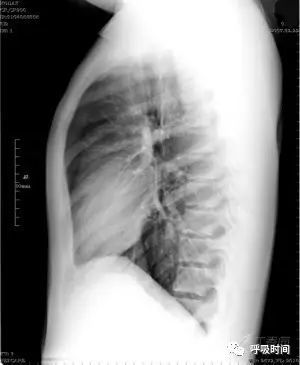

将一侧肺野平均划分为上、中、下肺野——红线;内、中、外带——黄线

1. 定位因为肺叶、肺段相互之间有重叠,所以仅有正位片时,除肺尖部病变可定位在上叶外,其他部位则以病变位于哪部分肺野的内中外带来做定位表述(图 4)。

图 4 将一侧肺野平均划分为上、中、下肺野——红线;内、中、外带——黄线

2. 定量:对气胸时肺压缩程度的判断,有学者研究,当肺压缩边缘位于肺野外带(胸腔/肺野外 1/3)时,肺压缩约为 50%,至中带时则肺压缩约为 75%。